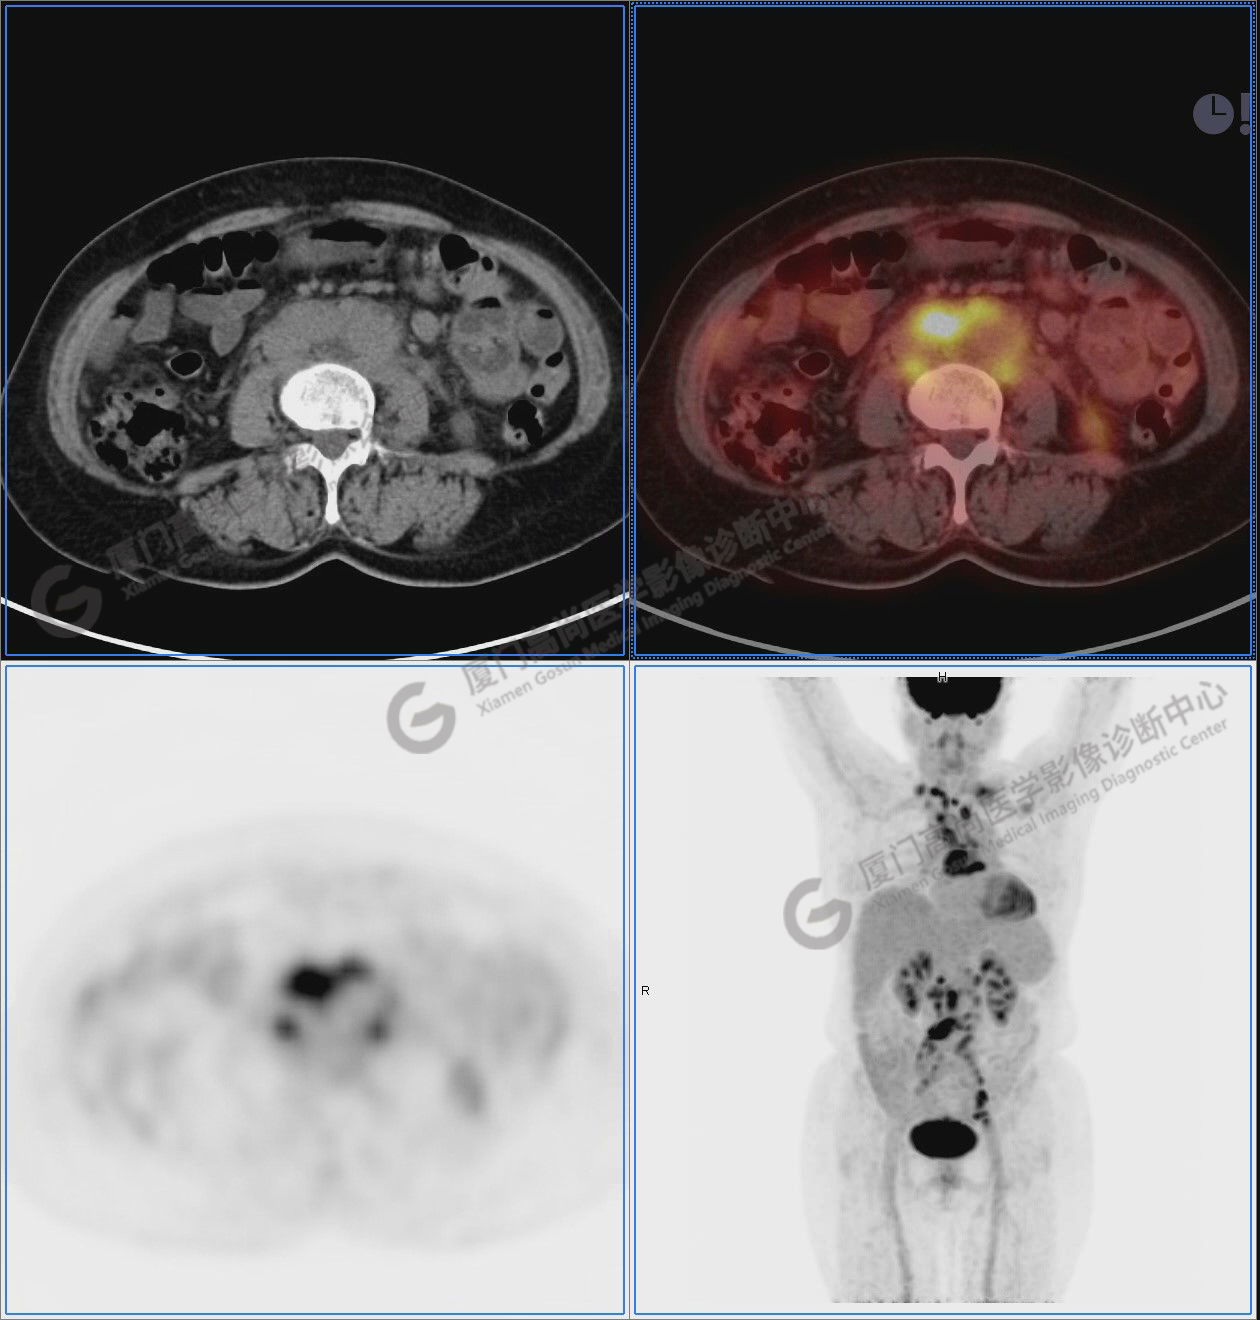

圖2-9:雙側(cè)鎖骨區(qū)、縱隔、右側(cè)內(nèi)乳區(qū)、腸系膜緣、腹膜后、雙側(cè)髂血管旁及盆腔多發(fā)腫大淋巴結(jié)影,代謝不同程度增高,考慮為轉(zhuǎn)移。

圖2

圖3

圖4

圖5

圖6

圖7

圖8

圖9